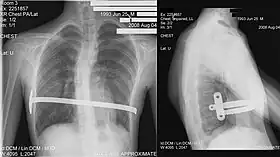

![]() X-Ray of a 15-year-old male after undergoing the procedure | |

Bar removal

After a period of two to four years,[3]: 343 the surgical stainless steel bar is removed from the patient's chest. This procedure lasts approximately ninety minutes. The length of time that the patient stays at the hospital following the bar removal procedure varies, depending on the amount of new bone growth surrounding the bar. Accordingly, the length of time may range from a few hours to several days, or up to one week.